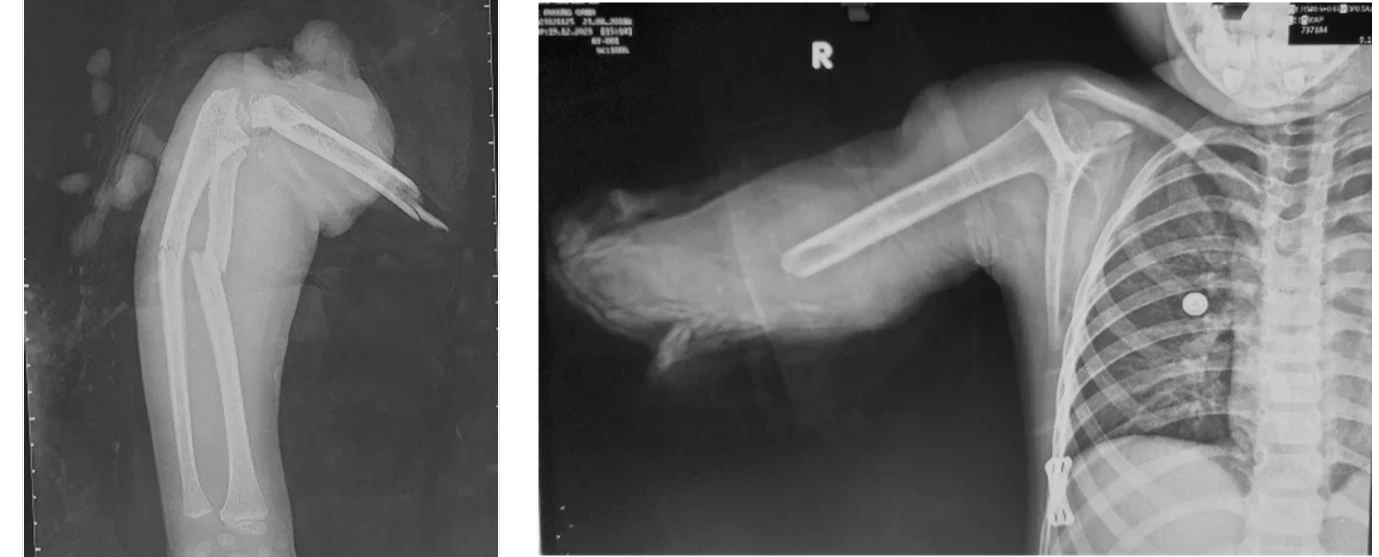

労働災害で切断された腕の再接合。

四肢再建三重大学形成外科。

列車事故で両腕切断の仏女性、再接合手術に成功 写真3枚 国際ニュース:AFPBB News。

タイグエン省:事故で両手切断の男性、接合手術が成功社会- VIETJOベトナムニュース。